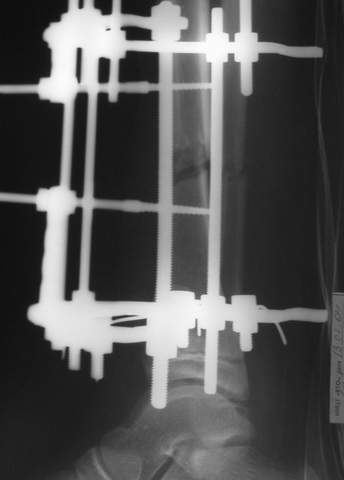

В аттачтах №№ 1 и 2 - примеры, когда 2 кольца не позволили послеоперационно

исправить смещение фрагментов большеберцовой (по ширине и вальгусное).

А казалось бы (#2) - поиграй на штангах и все влетит.

2

3a

3b

3c

В аттачте № 3 - один из примеров полукольцевого аппарат...

Это уже я баловался.

Итог? Работы больше (по времени и

интраоп "подгонке"), срастается также, а особого преимущества по сравнению с

"чиста" кольцевым (вес, удобство ношения и пр.) - я, по крайней мере,

не нашел.

Теперь не балуюсь.